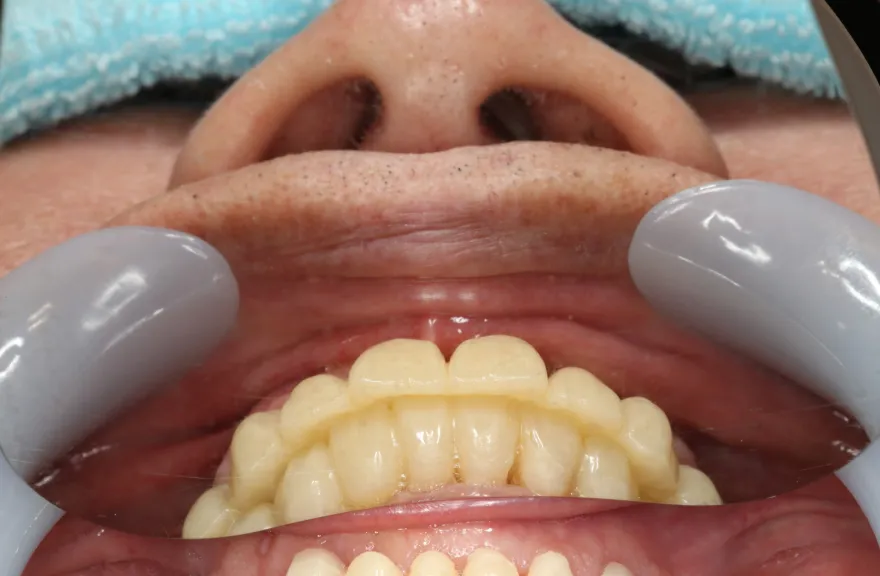

【治療例 5】上の歯がグラグラで困っている 62歳

- 相談内容

- 数年前に全体的に治療したが、上のつながっている歯がグラグラして噛めないということで来院されました。

- 治療費用・方針

-

上顎は5本の歯を保険のブリッジ治療で連結してある状態でした。どの歯の状態も良くなく、今回なんとか治療を行ったとしても近いうちに再びトラブルを起こしてくることが予想されました。

下顎は9本の歯が残っており、虫歯はあるものの差し歯として使える状況でした。

しかし、患者さんとの話し合いの中で、「数年前に行った治療なのに再び全てやりかえないといけないのは単純にしんどい。もうやりかえのないようにしたい」という患者さんの強い思いが伝わってきました。

今回で完全に治療をやり切ってしまい、今後は最小限の介入で歯科と付き合えるよう、上下顎残っている歯の全ての抜歯、必要な本数のインプラント埋入、上顎は総義歯形態で対応することとしました。 - 治療のリスク

インプラント治療は決して虫歯にはなりませんしかし歯周病にはなります。

ただ、歯を失った原因を考慮する必要があります。

この方はこれまで虫歯で歯を失ってきた方でした。残っていた歯は、特に下顎の歯は歯周病に侵されることなく今に至った方です。

そういった方がインプラント周囲炎になる状況はあまり考えにくく定期的なメンテナンスのみしっかり行っておけば今後の人生においてトラブルを起こすことは心配しなくて良いかと考えます。

上顎の総義歯は時間と共にすり減り、劣化していきます。

10年ごと程度でやりかえが必要な可能性がありますが、虫歯治療のようにお口の中でドリルを使って削ったりする必要はなく、歯型をとって技工士へ製作を依頼するだけなので、治療の負担は限りなく小さいと言えるでしょう。